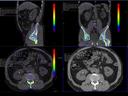

The question is: What makes True Dual Energy stand out? Look for these three criteria: crisp images with the option for even sharper contrast and significant artifact reduction; no extra dose in either Single Source or Dual Source Dual Energy scans, and a broad applicability for virtually all clinical questions and patients.

Discover Dual Energy (DE) spectral imaging. It’s the difference between images and answers. Visualization and characterization. Qualification and quantification. Built into all of our CT scanners, it delivers powerful performance, incredible versatility for your entire patient population, and exceptional ease-of-use – all while integrating seamlessly with your current workflow.